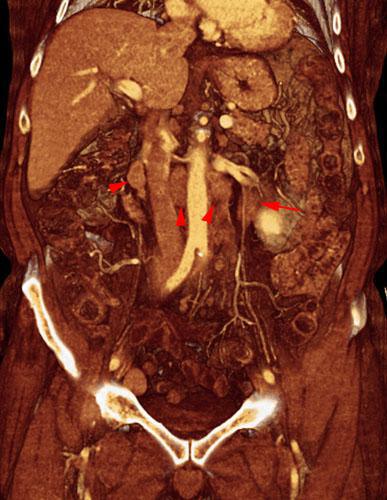

Hipernefroma muy vascularizado